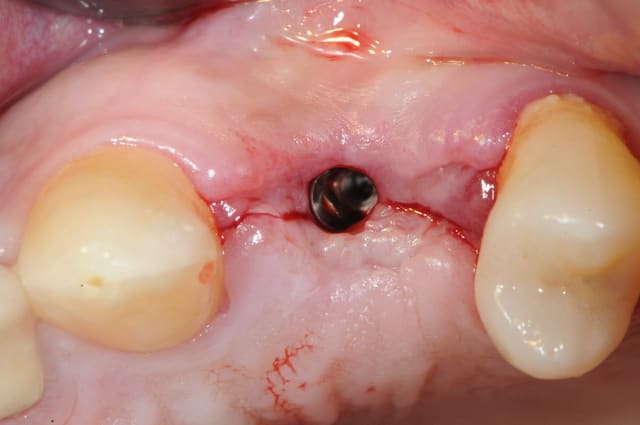

dis moi la tu le trouves comment mon compromis avec l'espace biologique

eii

d'après toi faites il y a combien de temps?

Superbe ratrapage suite à une operculisation d'une vis de couverture. Félicitations. Je te savais costaud béotien mais là tu m'impressionnes vraiment.

- pas de vis de couverture , pas d'operculisation!!

Même pas de lambeau pédiculé palatin!